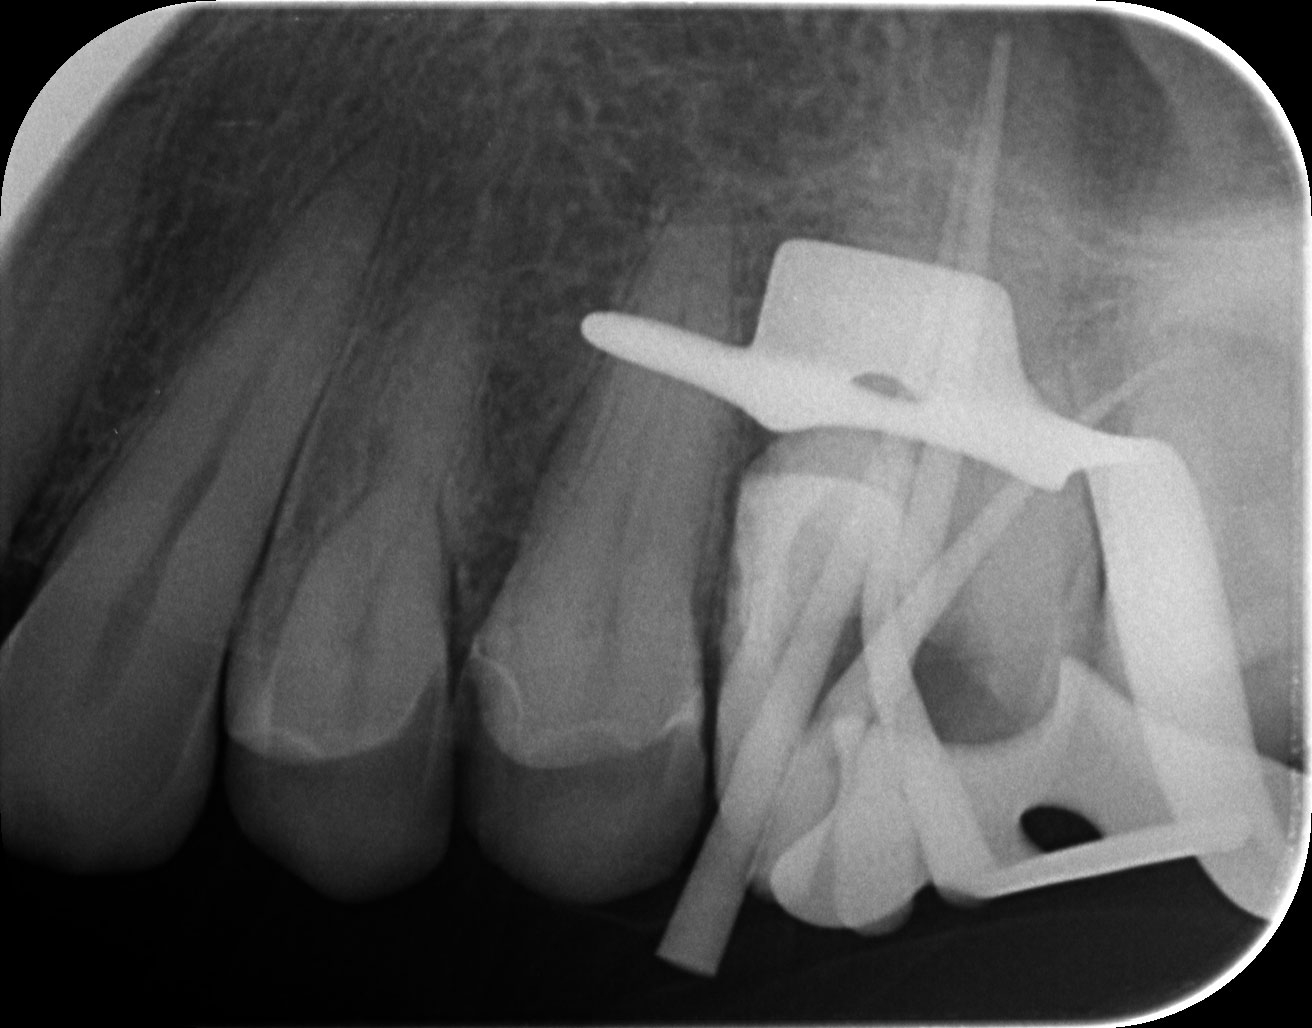

Dantų kanalų gydymas